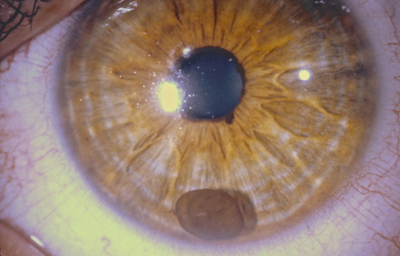

Nevus melanociticos en el Iris

Archivo Fotográfico Dr. Francisco Barraquer

Nevus melanociticos en el Iris

Archivo Fotográfico Dr. Francisco Barraquer

Nevus con escaso pigmento

Archivo Fotográfico Dr. Francisco Barraquer